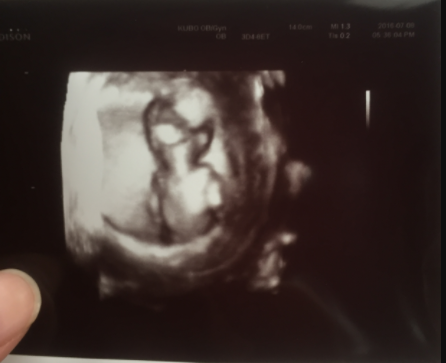

13週2日(13w2d・男の子)|kawakama さん(34歳)

エコー写真撮影時のエピソード:

ちょうどこの頃、仕事が大変な時で、また悪阻も辛い時期が続いており、妊婦生活にも慣れず、精神面も不安定な時期でした。

お腹の赤ちゃんも負担を感じているのではないかと不安だったのですが、健診の時のエコーで元気に動いて、そして「アイーン」のポーズを決めてくれた姿に緊張していた気持ちもほぐれ、和まされました。

お腹の中からエールをもらった気分でした!その時のエコー写真です。